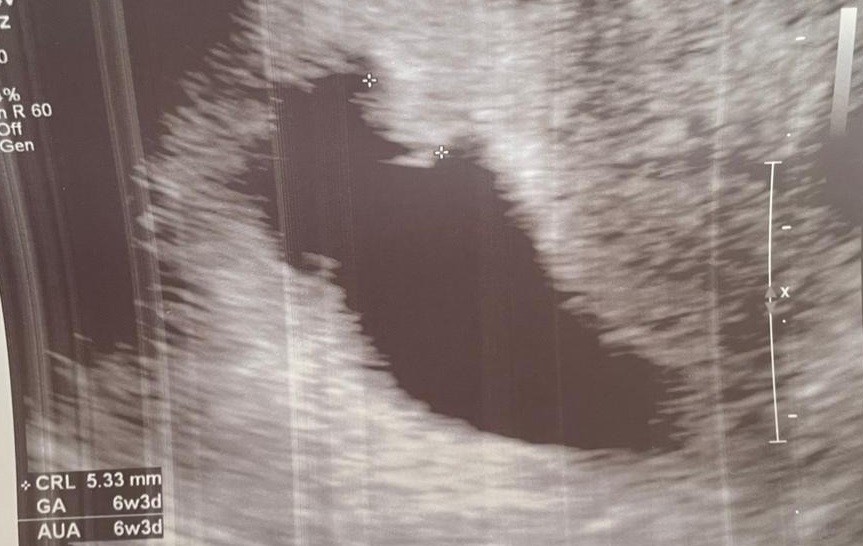

Mam zarodek z bijącym serduszkiem, to moja pierwsza ciążą i kompletnie to do mnie nie dociera:)

Załączniki

• Bez tytułu.jpg

Bez tytułu.jpg

88,6 KB · Wyświetleń: 131